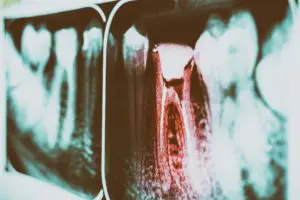

藉由顯微根管重新治療,重新救活一顆牙齒。 1 4 月, 2022 這種治療結果不是天天都看得到,很多時候得要靠運氣以及醫師的經驗。乍看兩張根管治療重新治療前後的X光片,一般患者大概看不出什麼差別,即使是牙醫師有時候也得改變拍攝角度去嘗試自己辛苦努力的成果。 閱讀更多 »